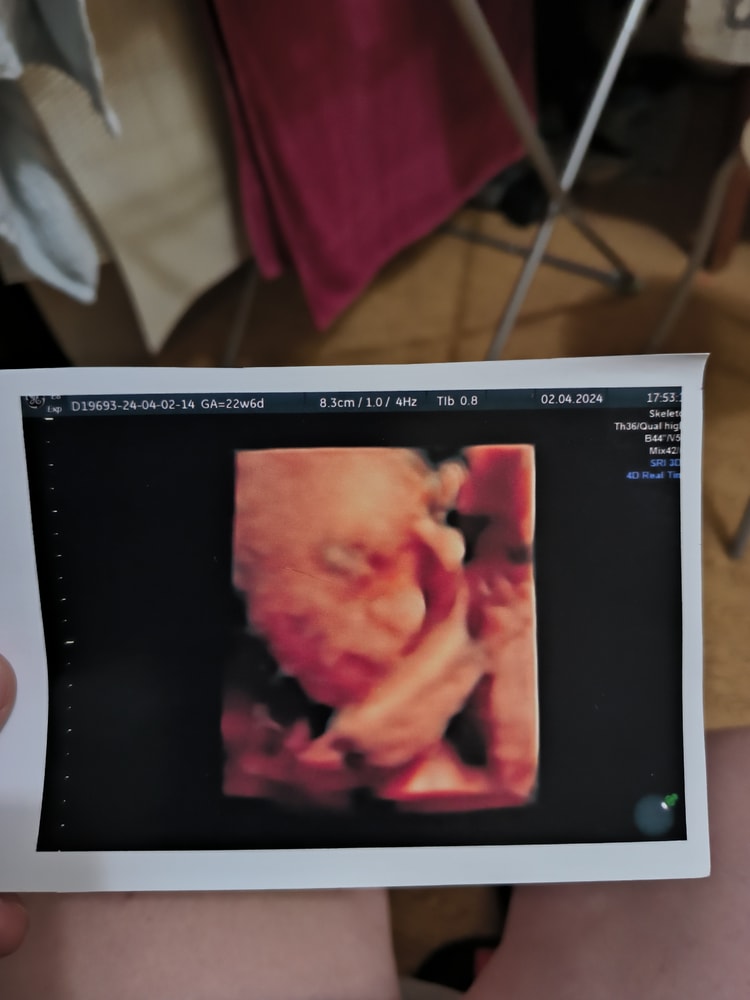

Я делала в 23 недели, честно такой инопланетянин был на фото 🤣 Изображение